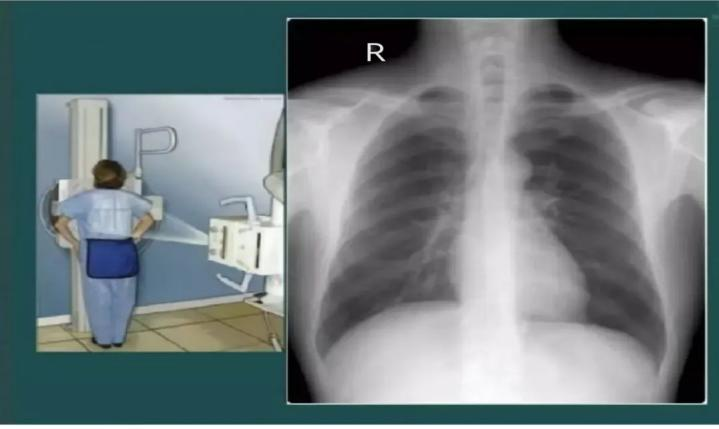

DR胸片检查

可有效筛查老年人常见的肺部感染、肺结核、肺结节、支气管扩张等异常情况,尤其对早期肺癌的发现具有重要意义。此外,DR胸片还可显示心脏大小、形态及周围血管情况,辅助判断心脏肥大、心包积液、主动脉弓钙化等,间接提示可能存在的高血压、动脉粥样硬化、心功能不全等心血管问题。

“听说拍DR辐射会致癌,每年一次身体受不了”。NO!NO!NO!DR胸片检查采用数字化技术,一次DR胸片的辐射剂量仅为安全阈值的1%-2%,大约只相当于乘坐几小时飞机在高空受到的天然辐射,或者晒两天太阳接受的日常环境辐射量。即使因病情需要,一年内复查3-5次,总剂量依然远低于安全上限。

检查前需去除身上的金属物品,女性脱去带有金属扣的内衣,脱去项链、耳环、手表等。